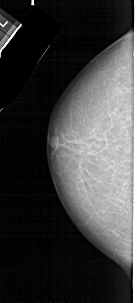

A_1579_1.RIGHT_MLO

RIGHT_MLO LINES 5086 PIXELS_PER_LINE 2551 BITS_PER_PIXEL 12 RESOLUTION 43.5 OVERLAY